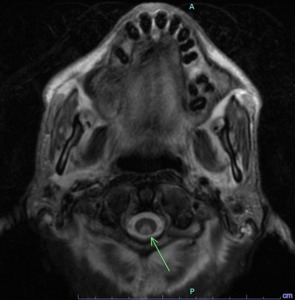

A 60-year-old patient presented with severe malnutrition and failure to thrive along with bilateral lower extremity weakness, cognitive dysfunction, and absent ankle reflexes on examination. He had macrocytic anemia with a mean corpuscular volume (MCV) of 117 fL . Vitamin B12 level was found to be less than 150 pg/mL (normal: 232-1245 pg/mL) with normal folate levels of 7.3 ng/mL (normal >4 ng/mL). Peripheral blood smear showed macrocytic normochromic red blood cells with mild anisopoikilocytosis and neutrophils with normal morphology (Figure 1). Magnetic Resonance Imaging (MRI) of the cervical spine with and without contrast showed a long segment mildly expansile cervical cord T2 signal hyperintensity predominantly involving the dorsal columns extending from the cervicomedullary junction to the C6 level measuring approximately 0.7 x 0.5 x 8.7 cm and associated diffusion restriction without enhancement (Figure 2). He was diagnosed with subacute combined degeneration of the cord due to Vitamin B12 deficiency, and was started on intravenous Vitamin B12 therapy. Further workup revealed a positive intrinsic factor blocking antibody suggesting pernicious anemia as the etiology.

Subacute combined degeneration of the cord is characterized by degeneration of the dorsal columns and the lateral columns of the spinal cord due to demyelination.1 It is most commonly caused by a deficiency in vitamin B12.2 Other causes include gastric abnormalities (gastric surgery/autoimmune gastritis/pernicious anemia), small bowel abnormalities, pancreatic disease, drug-induced, and genetic abnormalities. Vitamin B12 is necessary for maintaining neuronal myelin integrity. It acts as a cofactor for enzymes involved in converting homocysteine to methionine and methylmalonyl-CoA to succinyl-CoA which is necessary for myelin synthesis.1 It commonly presents with sensory deficits, paresthesia, weakness, ataxia, and gait disturbance, and in severe cases can lead to spasticity and paraplegia.3 MRI of the spine shows a very typical pattern with T2 hyperintense signal alterations usually confined to the posterior columns, which may involve the lateral columns and rarely the brainstem.4,5 Subacute combined degeneration of the cord is treated with parenteral cobalamin which is administered at a dose of 1000mcg once a week for one month, followed by 1000mcg once every month until clinical response is obtained.1